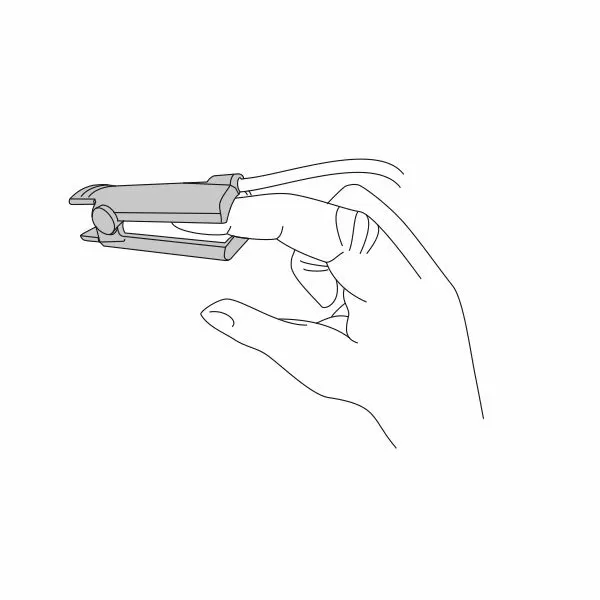

Почему может врать пульсоксиметр?

Причин, по которым пульсоксиметр может проводить измерения неверно, бывает несколько:

- у вас холодные руки. Согрейте их перед измерением;

- вы не до конца поместили палец внутрь прибора или измерению мешает длинный ноготь. Толстый слой гель-лака тоже может быть препятствием;

- вы долго находились в медицинской маске. Снимите ее, подышите глубоко и после этого делайте замер.